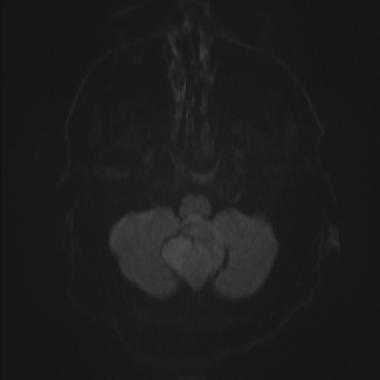

Были сделаны различные выводы касательно роли диффузионно-взвешенной МРТ. Измеряемый коэффициент диффузии (ИКД) для высокодифференцированных опухолей обычно оказывался ниже по сравнению с окружающей тканью головного мозга. Некоторые исследования показали схожую тенденцию в случае менингиом, но по данным других исследований значения ИКД для 1-й и 2-й степеней злокачественности статистически достоверно не различались.

Менингиома задней черепной ямки: диффузионно-взвешенное МР-изображение (DWI). Сигнал умеренно повышен, что соответствует умеренному ограничению диффузии.